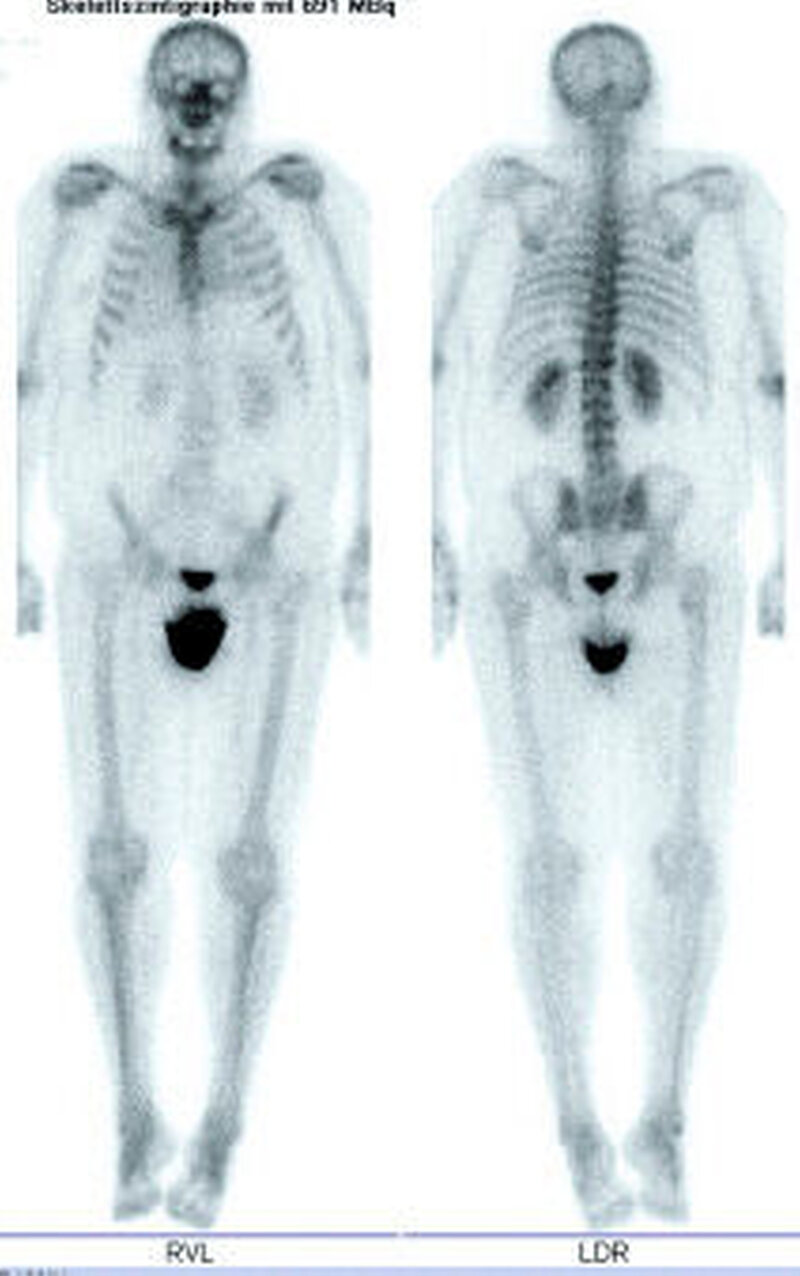

Dreiphasen-Szintigrafie: Die planare Dreiphasen-Szintigrafie mit 99m Tc-markierten Bisphosphonaten ist ein nuklearmedizinisches Standardverfahren in der Diagnose der Kieferosteomyelitis/-nekrose. Sie zeigt die Lokalisation von vermehrtem Knochenumbau (Osteoblastenaktivität) mit hoher Sensitivität an (Abbildung 6). Das Verfahren ist jedoch nicht spezifisch und hat nur eine begrenzte Ortsauflösung [Stockmann et al., 2010].

SPECT(single photon emission computed tomography)-Technik: Die diagnostische Akkuratesse der Szintigrafie kann durch Verwendung der SPECT gesteigert werden (Abbildung 2) [Dore et al., 2009]. Hier werden anders als in der Szintigrafie (in der Aufnahmen aus ventraler und dorsaler Projektion aufgenommen werden) mehrere Aufnahmen aus unterschiedlichen Winkeln akquiriert, aus denen ein dreidimensionales Bild errechnet wird. Dies verbessert die Detektion und die örtliche Zuordnung von fokal vermehrten Traceranreicherungen im Vergleich zu Szintigrafie oder CT allein [Bolouri et al., 2013].

Neben den bekannten Bisphosphonaten werden zunehmend Fälle von Kiefernekrosen auch durch Denosumab, einen RANKL-Antagonisten, beobachtet. Deswegen sollte speziell auch nach den Medikamenten Prolia©und XGeva©vor oralchirurgischen Eingriffen gefragt werden. Während Prolia©in der Osteoporosetherapie Anwendung findet, wird XGeva©bei Prostata- und Mammakarzinompatienten subkutan verabreicht und hat speziell auch bei Nierenfunktionsstörungen seine Indikationen. Die Halbwertszeit von Bisphosphonaten beträgt bis zu zehn Jahren, die von Denosumab in der Regel zwischen 80 und 120 Tagen [Ruggiero, 2013]. In direkten Vergleichsstudien bei onkologischen Patienten werden etwas mehr gehäuft Nekrosen durch Denosumab als durch Zoledronat (Aminobisphosphonat) festgestellt. Die Erfolge einer definitiven Heilung waren jedoch bei den Denosumabnekrosen scheinbar besser [Saad et al., 2012; Van Wyngaert et al., 2011]. Als Hauptursachen einer Kiefernekrose sind bei beiden Präparaten nach wie vor Zahnextraktionen zu nennen. Das zweitgrößte Risiko durch Prothesendruckstellen wird jedoch häufig unterschätzt (Abbildungen 5 und 6) [Hoefert, 2012].